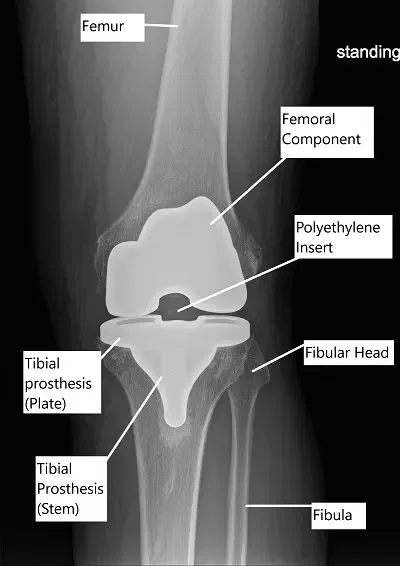

Radiografía que muestra una prótesis total de rodilla.

Componentes protésicos de prótesis total de rodilla

La imagen muestra los componentes protésicos formados por componentes tibiales y femorales metálicos de aleación de cromo-cobalto e inserto de polietileno. El componente femoral y el inserto son de retención cruzada. La elección entre el implante de retención cruzada y el implante estabilizado posterior depende de la enfermedad de la articulación de la rodilla y de la integridad del ligamento cruzado posterior.